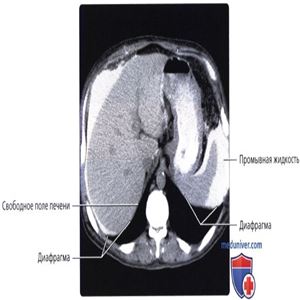

КТ с контрастированием, исследование пожилого мужчины с почечной недостаточностью, получающего перитонеальный диализ, представлены первые шесть срезов. К диализату была добавлена контрастная среда для определения потенциальных областей инкапсулированных скоплений жидкости, что обусловливает белый цвет жидкости. Обратите внимание на внутрибрюшинные скопления жидкости в поддиафрагмальных пространствах.

Обратите внимание, как печень и селезенка подвешены на диафрагме, за счет чего они не соприкасаются со стенкой грудной клетки. Свободное поле печени напрямую контактирует с диафрагмой, но не брюшинной полостью и, соответственно, промывная жидкость не контактирует со свободным полем.

Жидкость проникает в щель серповидной связки. Обратите внимание на отсутствие жидкости в сальниковой сумке. В большинстве случаев за исключением тех, когда